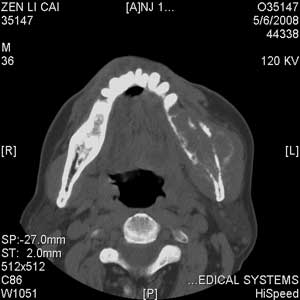

以下是引用jiangjing在2008-5-28 15:56:00的发言:[br]下颌骨左侧部骨质破坏,轻度膨胀,瘤骨形成,软组织肿胀考虑 恶性骨肿瘤-----肉瘤类